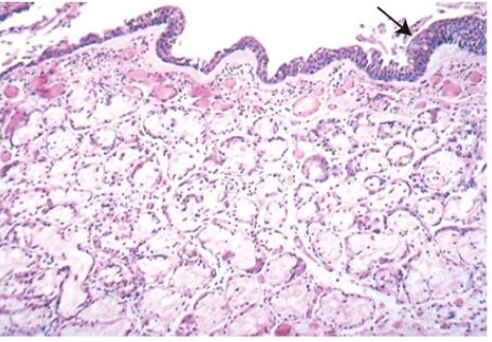

Que représente cette image + coloration ?

A

-Bronchite chronique. On remarque l’épaississement marqué de la couche muqueuse (environ deux fois la normale) et la métaplasie squameuse de l’épithélium pulmonaire (flèche noire).

- Coloration H & E